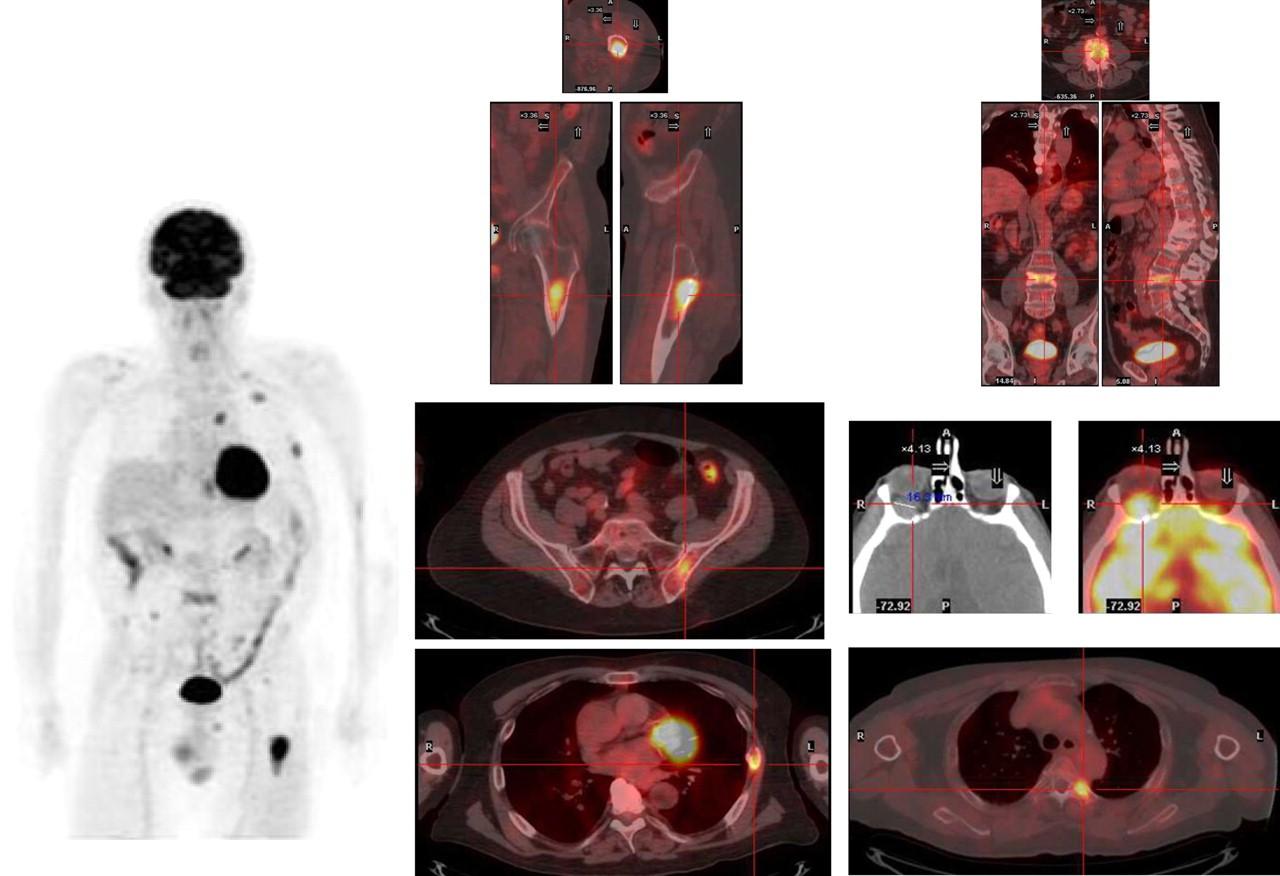

PET/CT Imaging in MM

Stewart AK et al. Blood. 2009;114:5436. San Miguel JF et al. ASCO Educational Book. 2013;e313.